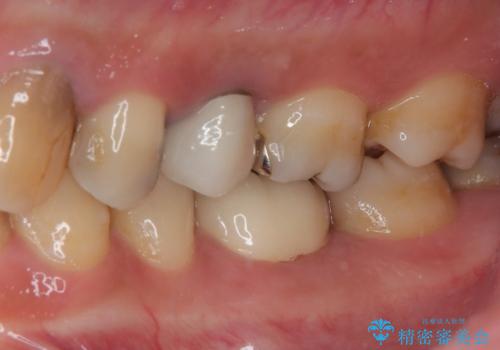

- 左下の詰め物が割れたとのことで来院された患者様です。現在に至るまで二度セラミックの詰め物(セラミックインレー)が割れているので強度面を考慮しセラミックの被せもの(セラミッククラウン)にて治療を行っていくことにしました。

拡大鏡視野下でセラミックインレー、虫歯の除去を行い、オールセラミッククラウンに適した形に整えました。

機能面、見た目共に満足していただきました。今後はメンテナンスで通っていただく予定です。